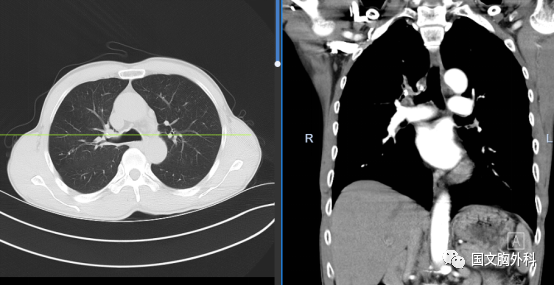

周大爺,發(fā)現(xiàn)肺占位1個月。CT下觀察右肺上葉腫物延續(xù)至肺門,穿刺病理提示:肺鱗癌。有手術(shù)機會,家屬同意手術(shù)治療。

術(shù)中患者右肺門分離困難,決定行右肺上葉袖型切除,在長達(dá)8小時的奮斗后,周大爺手術(shù)順利結(jié)束。